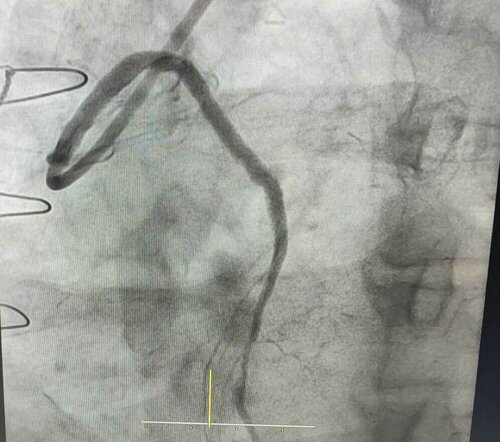

Complex LAD Angioplasty Performed by Dr. Hasmukh Gujar

Dr. Hasmukh Gujar successfully performed a complex angioplasty at Bharti Hospital, addressing a challenging case of LAD-CTO in the proximal segment. D...